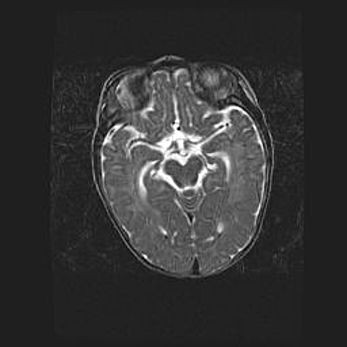

Неполная лизэнцефалия (пахигирия). Открытая гидроцефалия.

Возраст: 17 дней

Вес: 3110 г

Пол: мужской

Окружность головы: 33,5 см

Срок гестации: 35-36 недель

Лизэнцефалия—недоразвитие корковой пластинки и мозговых извилин в результате нарушения миграции нейронов коры. Поверхность мозговых полушарий гладкая. Микроскопически выявляется отсутствие нормальных слоев коры и скопление групп нейронов в подкорковом белом веществе.

Пахигирия—уменьшение числа вторичных извилин. В пораженном полушарии нервные клетки образуют толстый недифференцированный слой с неправильно расположенными нервными волокнами и группами гетеротопных клеток. Нервные клетки незрелые. Белое вещество истончено. При этом нередко аномально развит корково-спинномозговой путь.